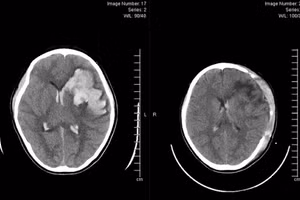

Bệnh nhi xuất huyết não do vỡ khối thông động tĩnh mạch não (AVM). Ảnh: BVCC.

GD&TĐ - Vừa qua, Bệnh viện Bãi Cháy đã cứu sống một bệnh nhi bị xuất huyết não nguy kịch do vỡ khối dị dạng thông động tĩnh mạch não (AVM) não.